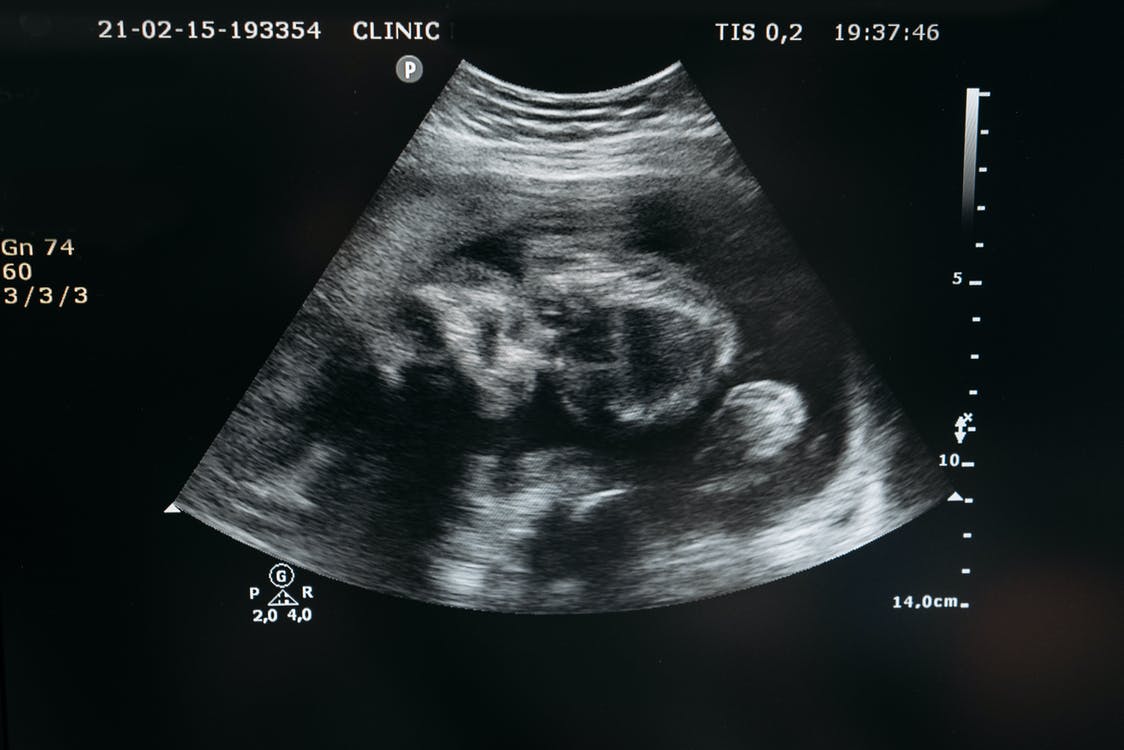

#0162的B型超声检查成像。此前母体刚跑完21 km的半程马拉松。摄于2010/02/10

完成聚集后的对象会在9:00 AM同时出发,并依照半程马拉松规程完成整场比赛。在此过程中,对象会避开人流密集场所和人流高峰时段。虽然对象通常处于早期妊娠,但在比赛过程中均表现出了典型中晚期妊娠的症状,包括但不限于子宫明显增大、自觉胎动和胎儿心音等。值得注意的是,剧烈运动并未对其胎儿造成直接影响。